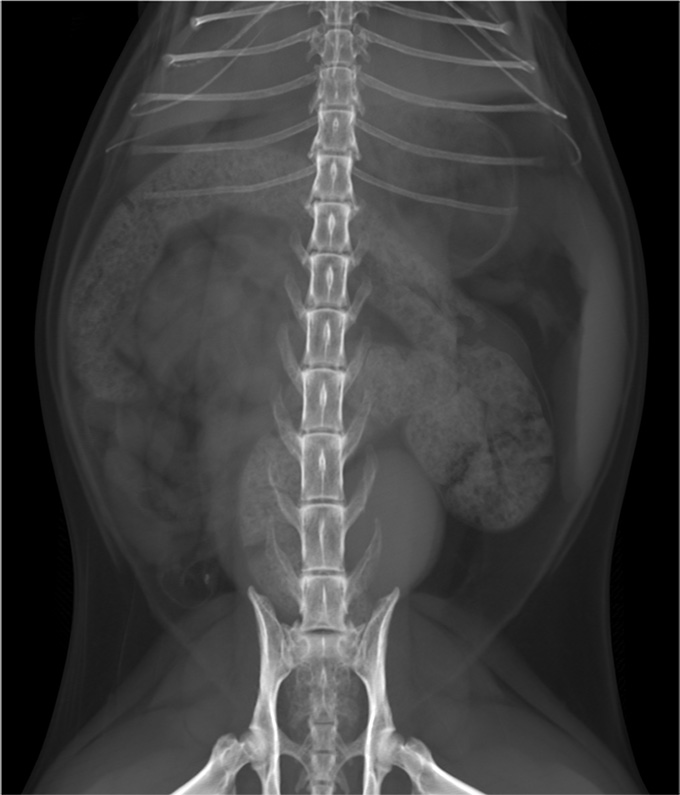

abdo chat VD

Ventrodorsale